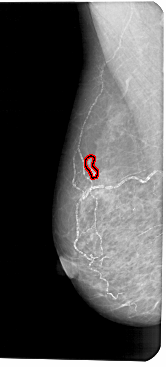

A_1191_1.LEFT_MLO

LEFT_MLO LINES 5491 PIXELS_PER_LINE 2476 BITS_PER_PIXEL 12 RESOLUTION 43.5 OVERLAY

FILE: A_1191_1.LEFT_MLO.OVERLAY

TOTAL_ABNORMALITIES 1

ABNORMALITY 1

LESION_TYPE CALCIFICATION TYPE PLEOMORPHIC DISTRIBUTION LINEAR

ASSESSMENT 4

SUBTLETY 2

PATHOLOGY MALIGNANT

TOTAL_OUTLINES 1

BOUNDARY